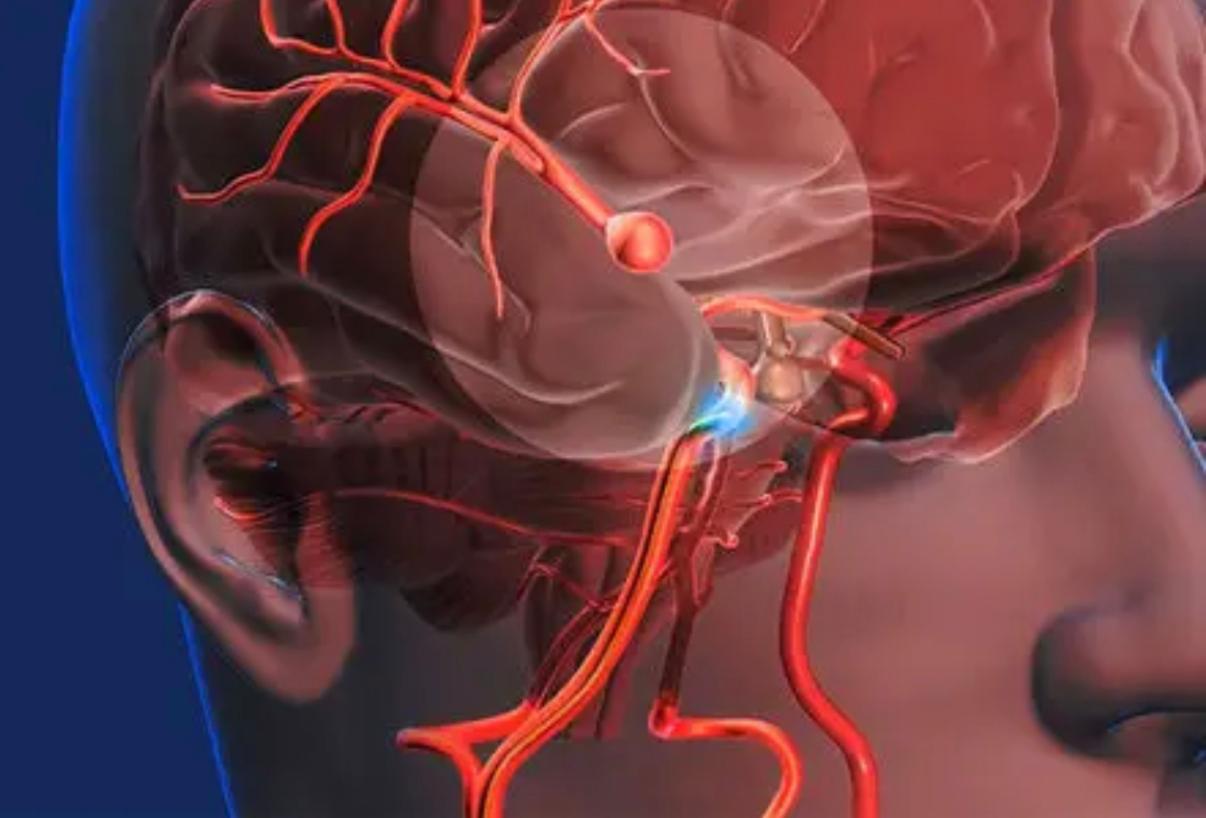

A neurocirurgia vive uma nova fase com o avanço das técnicas minimamente invasivas. O tratamento endovascular, que dispensa a abertura do crânio, já se consolidou como uma das principais alternativas para pacientes com aneurisma cerebral, dilatações nas paredes das artérias do cérebro que podem causar hemorragias fatais quando se rompem.

O aneurisma cerebral é uma dilatação localizada na parede de uma artéria, provocada pela fragilidade da estrutura do vaso. Pode variar de poucos milímetros a mais de dois centímetros e, em grande parte dos casos, não apresenta sintomas. Quando se rompe, provoca uma hemorragia subaracnóide, quadro grave que pode levar à morte.

No procedimento conhecido como embolização, o neurocirurgião realiza uma pequena incisão na virilha e insere um cateter fino que percorre o sistema vascular até o cérebro. No local do aneurisma, são aplicados dispositivos como espirais metálicas (coils) ou stents, que bloqueiam o fluxo sanguíneo dentro da dilatação e impedem o rompimento.